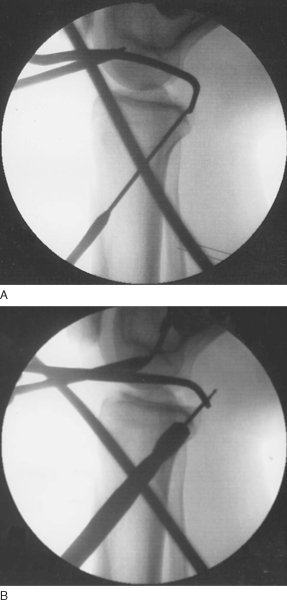

Radiographs of the knee are obtained to inspect for any fracture in the acute setting or for any medial or patellofemoral compartmental arthrosis in the chronic setting. Long-cassette films should be obtained if any fixed or dynamic instability is suspected. Posterior tibial subluxation can sometimes be seen on the lateral radiograph. Otherwise, a comparative stress lateral radiograph can also be obtained (

Fig. 67-2

).

Figure 67-2 (demonstrated by the arrows) |